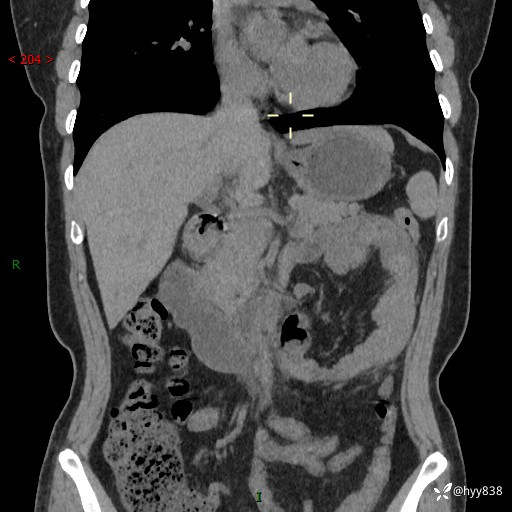

现病史:患者1天前无明显诱因下出现左上腹部及腰背部胀痛不适,阵发性加剧,伴肛门停止排气;无发热,无恶心呕吐,无畏寒发热,无心慌气短等不适,于当地市第二人民医院就诊,行腹部ct检查提示左上腹区肠系膜血管从剧聚集,分布紊乱伴肠管局限性稍扩张积液,不完全性肠梗阻;考虑子宫颈纳氏囊肿,双侧附件区囊状灶;予以抗炎及对症支持等治疗后未见明显缓解,现患者为求进一步治疗来我院急诊就诊,遂以“肠梗阻”收住入院。 病来,神志清,精神可,饮食睡眠不佳,经灌肠后排便2次,小便正常,体力体重无明显变化。

上腹部CT平扫